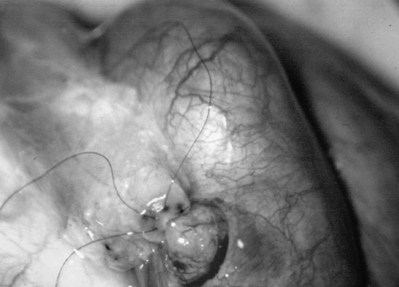

Inguinal hernia repair, particularly when performed in childhood, is known to be associated with vasal injury leading to obstruction. If there is no previous inguinal incision and the side of obstruction is unknown, the testis is delivered through a high vertical scrotal incision (see Scrotal later). The vas deferens is identified and isolated at the junction of the straight and convoluted portions of the vas deferens. Using an operating microscope and 10-power magnification, the vasal sheath is longitudinally incised and the vasal vessels carefully preserved (Fig. 22–3A).

Figure 22–3 A, Using an operating microscope and 10× magnification, the vasal sheath is longitudinally incised and vasal vessels carefully preserved. B, Under 25× magnification, a 15-degree microknife is used to hemitransect the vas until the lumen is revealed.